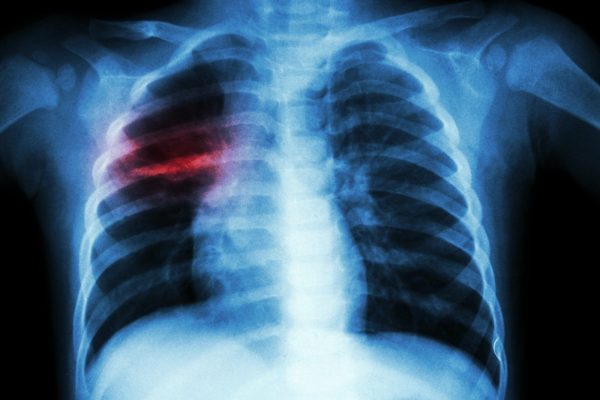

Respublikinės Panevėžio ligoninės Infekcinių ligų korpuso Pulmonologijos skyriuje pastarąjį pusmetį visos lovos užimtos tuberkulioze sergančių ligonių, du jų per paskutinę savaitę mirė. Ieškodami būdų paskatinti žmones gydytis nuo šios itin pavojingos ligos, medikai siūlo net ir prekybos centrų dovanų čekius.

Tuberkuliozė – viena seniausiai žinomų infekcinių ligų. XVI–XIX a. ji vadinta didžiuoju baltuoju maru ir anuomet nulėmė visą penktadalį ankstyvų mirčių. Apie ligos gydymą buvo mažai žinoma iki bakterijos atradimo XIX a. pabaigoje ir antibiotikų atsiradimo XX a. pradžioje.

Užkrečiamųjų ligų ir AIDS centro duomenimis, per pirmąjį šių metų ketvirtį mūsų šalyje užregistruota 11 mirties nuo tuberkuliozės atvejų. Jauniausiam mirusiajam nuo tuberkuliozės asmeniui – 32, vyriausiam – 94 metai.

Europos ligų prevencijos ir kontrolės centro duomenimis, 2017 metais Europos Sąjungos šalyse nuo šios ligos mirė 4000 žmonių. Mirtingumo rodiklis siekė – 0,8 atv. 100 tūkst. gyventojų. Aukščiausias šis rodiklis buvo Lietuvoje – 5,8 atv. 100 tūkst. ir Rumunijoje – 4,7 atv. 100 tūkst. gyventojų.

Respublikinėje Panevėžio ligoninėje iš viso regiono per metus gydosi vidutiniškai apie 160 pacientų, sergančių įvairios formos plaučių tuberkulioze. Tačiau pastarąjį pusmetį stebimas susirgimų šia liga padažnėjimas – 40 Infekcinių ligų korpuso Pulmonologijos skyriaus lovų, pasak laikinai skyriaus vedėjos pareigas einančios Salvijos Vilutienės, beveik nuolat būna užimtos.

„Anksčiau buvo šioks toks apmažėjimas, bet pastaruoju laiku – pilnos lovos. Dabar skyriuje guli 35 ligoniai. Dažniausiai dabar pas mus patenka pacientai dėl atviros, itin uždelstos, į visus organus išplitusios ligos formos“, – sakė vedėja.

Jos teigimu, tuberkuliozė pažeidžia ne tik plaučius. Ši klastinga, iš pradžių nejuntama liga per ilgą laiką negydoma išplinta po visą kūną ir nepasiekia tik plaukų bei nagų.

Išplitus tuberkuliozei žmogui padėti būna labai sunku. Per pastarąjį pusmetį Panevėžio ligoninėje jau mirė ne vienas toks ligonis. Prieš tai buvusią savaitę užgeso dviejų tuberkulioze sirgusių asmenų gyvybė, vienas iš jų, jaunas, vos trečią dešimtį peržengęs panevėžietis, mirė sekmadienį.

Sergant lengvesne ligos forma stacionarus jos gydymas ligoninėje trunka 4 mėnesius, o esant atvirai tuberkuliozei – net metus.